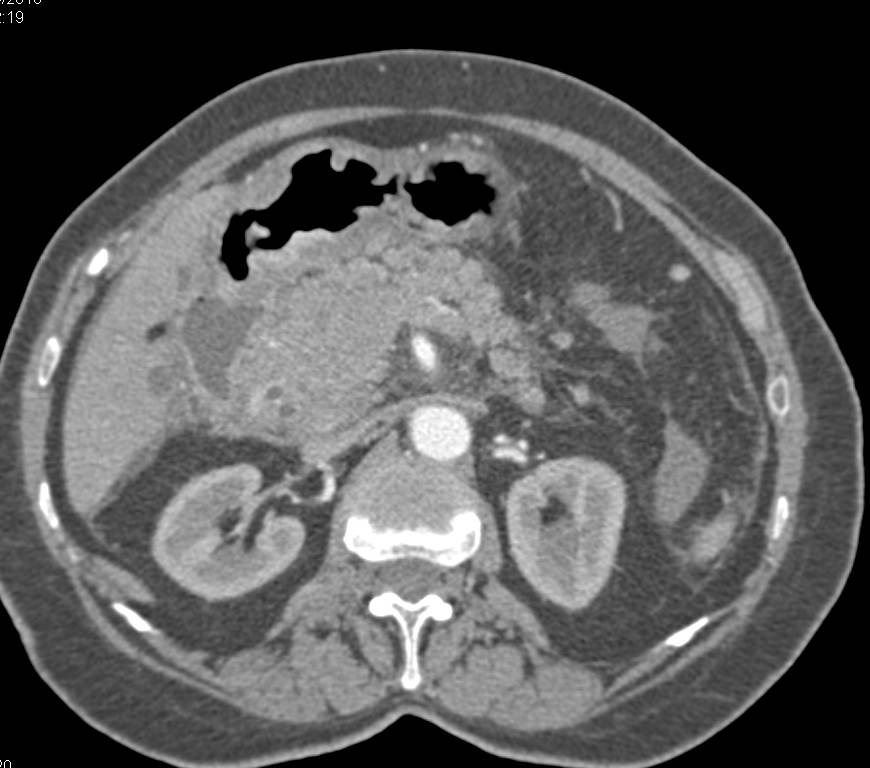

Subtle Gastric Cancer with Liver Metastases